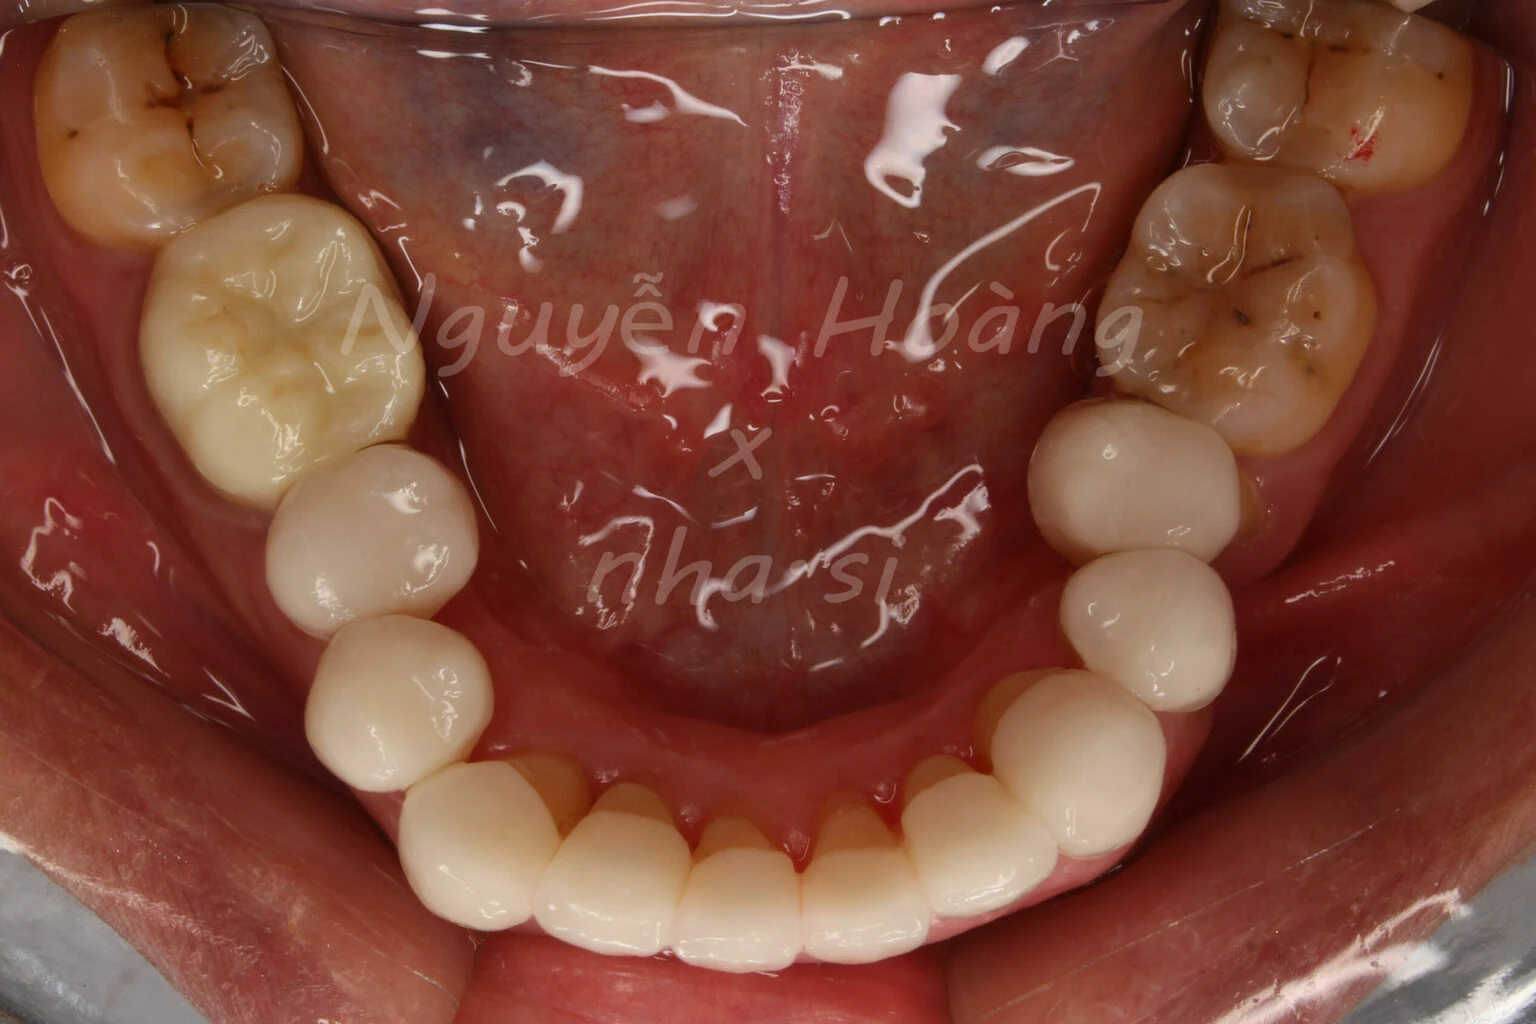

Hình 2: Mẫu hàm sơ khởi. Sử dụng mẫu hàm sơ khởi để chẩn đoán và lên kế hoạch phục hình.

Nhìn trên mẫu hàm sơ khởi, chúng ta có thể thấy điểm khó khăn trong mài chụp răng 35, 45 ở đây là do nhiều yếu tố. Răng nghiêng trong, nếu muốn mài tới cổ răng thì sẽ phải lấy rất nhiều mô men ở phía trên, và đồng nghĩa với việc phải điều trị tủy. Khoảng phục hình ở vị trí răng 5 chỉ tương đương với ⅔ kích thước của chính nó nếu dựng trục lên. Phía xa răng 4 phải mài nhiều hơn để có khoảng để phân bổ đắp sứ cho răng 4 và răng 5, tạo thuận lợi cho việc với sứ răng 5 ra phía ngoài. Mài đường hoàn tất phía gần răng 5 có nguy cơ phạm phải đường hoàn tất phía xa răng 4. Tiêu mòn cổ răng 4 và răng 5 ảnh hưởng độ dày và tính liên tục của đường hoàn tất). Điểm thuận lợi duy nhất ở đây chính là khớp cắn. Răng trên không chiếm khoảng phục hình răng 5 và các răng trên đều sẽ làm chụp, nên hoàn toàn có thể có khoảng không gian mặt nhai mong muốn. Có lẽ là thiếu sót nếu không kể tới một điểm thuận lợi mang tính chiến lược, đó là khách hàng đòi hỏi nhiều nhưng lại tin tưởng vào tay nghề của tôi!